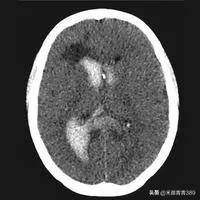

2022-09-22 01:43 阅读: 评论:脑出血是指原发性非外伤性脑实质出血,占急性脑血管病的20%~30%,约80%的出血部位发生在大脑半球,约20%的出血发生在脑干和小脑,发病年龄多在50岁以上,根据出血部位不同可分为,基底节区出血,丘脑出血,脑叶出血,脑干出血,小脑出血和脑室出血七种。根据病因不同,可分为原发性脑出血和继发性脑出血。根据出血量多少不同,临床症状轻重不同,严重者可昏迷,危及生命,一般脑出血症状表现有头疼,头晕,恶心,呕吐,言语不利,视物模糊,肢体活动障碍,意识改变,出现上述症状高度怀疑脑出血,尤其是平时血压高,和年龄大的患者,需要迅速到医院就诊,进行脑CT检查,当确诊脑出血后,立即住院治疗,住院后常规给予稳定血压,脑脱水降低颅内压和相关治疗。比较严重的脑出血是脑干出血,脑室出血,和出血量大患者,

死亡率比较高,大部分脑出血患者在内科药物保守治疗,出血量比较大的脑出血,脑室出血,需要外科开颅手术,或者颅穿引流,降低颅内压,防止脑疝形成。脑出血预后,与出血部位,出血量多少以及是否有合并症相关。一般急性期七天,两周后病情逐步稳定,经过积极治疗,绝大部分患者可以好转出院。脑出血康复和预防,要特别注意血压,控制血压在正常水平,要戒烟戒酒,清淡饮食,避免劳累,控制体重,规律休息,适当运动,稳定血糖血脂。